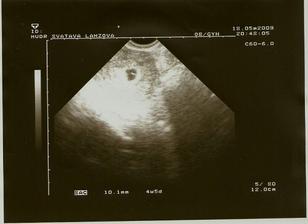

18. května - potvrzeno těhotenství u paní doktorky, jsme v 5tt. Zatím je to malý fazoleček 🙂 Za tři týdny jdu jdu na kontrolu a už by mělo jít slyšet srdíčko. Mazééééééc! 🙂))

9. června - kontrola u paní doktorky proběhla bez potíží, miminko krásně roste, jsme v 8tt+4. Termín porodu je 11.1. s tím, že mám počítat o týden déle kvůlu delšímu cyklu. Odebrána krev, výsledky se dozvím za 3 týdny při další kontrole. Srdíčko bilo prostě nádherně!!! Jsem naměko 🙂 Je to fakt zázrak.